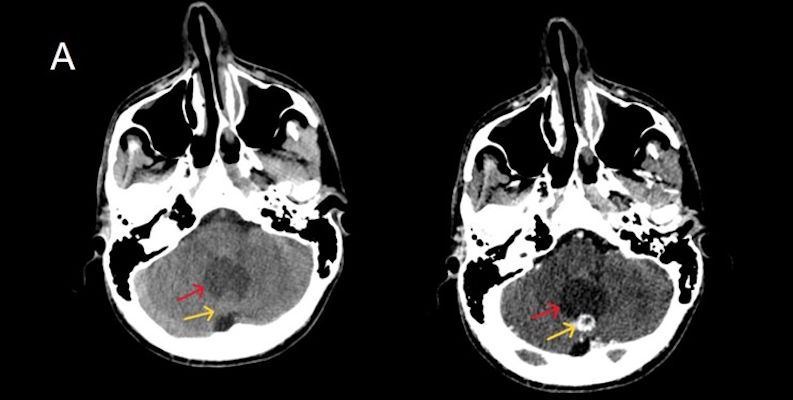

- A) Beyin BT incelemede; posterior fossada hipodens, düzgün sınırlı kistle beraber (oklar), posteriorunda 8 mm boyutunda, iyi sınırlı, kontrastsız BT’de parankim ile izodens, postkontrast görüntülerde yoğun kontrast tutulumu gösteren mural nodül komponenti (oklar) gözlenmektedir.